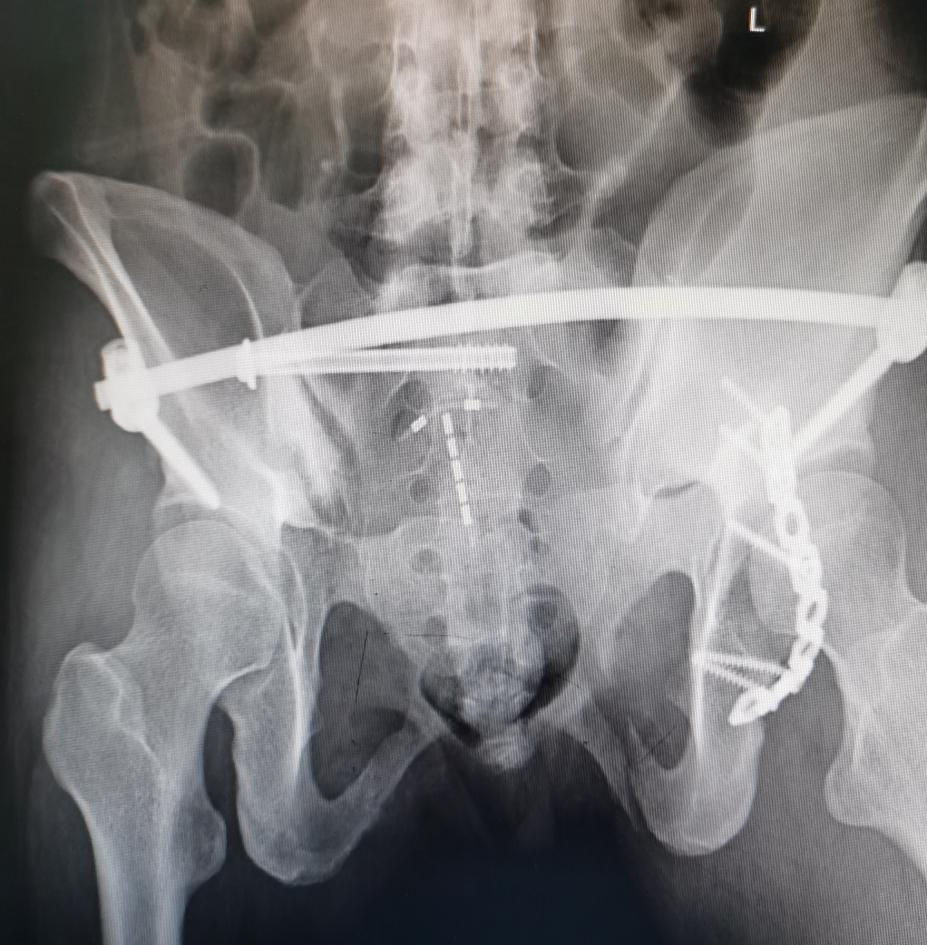

宜安科技:镁骨内固定螺钉注册正按要求推进

图片来源于网络,如有侵权,请联系删除